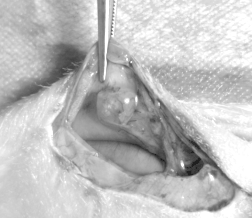

1、生殖器官外观:小鼠生殖器官在不同动情周期阶段有变化,如子宫颜色和大小、卵巢大小等,但观察需解剖小鼠,会造成伤害。

1、用显微镊卷米粒大小棉絮,沾湿生理盐水,插入小鼠阴道口 0.5 - 1cm,贴阴道壁从里往外刮 10 次(大鼠用棉棒,且保持每只鼠力度与次数一致)。